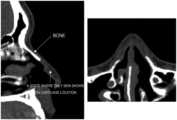

FIGS.1(a) and1(b) illustrate CT images taken from the side of the face and from below the chin.

FIGS.1(a) and1(b) illustrate CT images taken from the side of the face and from below the chin, andFIGS.2(a)-2(c) illustrate 3-dimensional images of the skin, bone, and nasal cavity, that have been segmented from the CT images ofFIGS.1(a) and1(b).

FIG.1(a) illustrates a CT image taken from the side of the face, andFIG.1(b) illustrates a CT image taken from below the chin. Generally, it is possible to identify bones, empty spaces inside the body, and skin from the CT images, but not cartilage. For reference, here, it should be noted that bone does not refer to cartilage but hard bone that is identifiable from a CT image. Thus, as shown below, the present disclosure will model the shape of a nasal cartilage that is not identifiable from a CT image, by applying information of anatomy to images identifiable from the CT image, and model the inner shape of a nasal implant, which is a surface where the nasal implant may be seated, based on the modelled nasal cartilage.

Next, offset of an appropriate value is applied to the imageFIG.3(b) to expand the image of the nasal cavity, thereby expanding the size of the nasal cavity (FIG.3(c)). Here, as illustrated inFIG.4, with the 3-dimensional image of the nasal bone and the image of the nasal cavity expanded by applying offset placed to overlap each other, whether the expanded nasal cavity has identical height of the nasal bone is compared (the part inFIG.4 indicated with a circle), and while adjusting the offset value such that the expanded nasal cavity has the identical height as the nasal bone (this may mean the expanded nasal cavity and the nasal bone being connected naturally without any step), an image of the expanded nasal cavity is obtained.